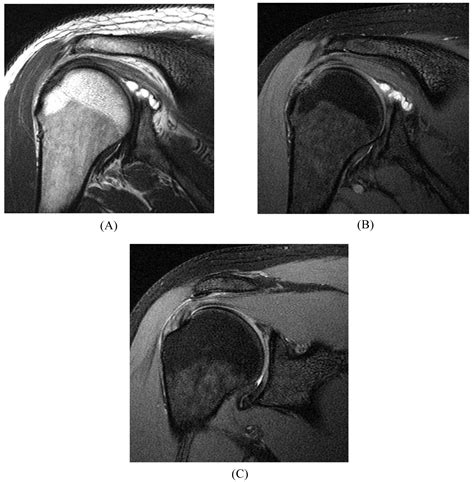

An MRI is a non-invasive imaging technique that uses magnetic fields and radio waves to produce detailed images of the body’s internal structures. For diagnosing a Slap Tear MRI, the scan provides high-resolution images of the shoulder joint, allowing radiologists to identify tears in the labrum and other soft tissue injuries.

To enhance the visibility of the labrum and other soft tissues, contrast agents may be used. These agents are injected into the shoulder joint before the MRI scan, highlighting any abnormalities or tears in the labrum.

Slap Tear MRI scans are particularly useful for diagnosing SLAP tears because they provide clear images of the labrum and surrounding structures. However, interpreting the results requires expertise, as SLAP tears can be subtle and easily missed.

Interpreting the results of a Slap Tear MRI involves a thorough examination of the images by a radiologist. Key findings that indicate a SLAP tear include:

• Abnormal signal intensity within the labrum, suggesting a tear.

• Displacement or detachment of the labrum from the glenoid.

• Fluid or contrast agent extending into the tear, highlighting the extent of the injury.